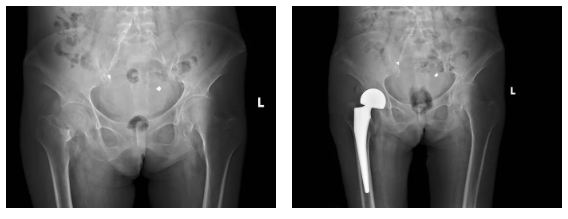

术前,麻醉科副主任龚拯采取超声引导下单次腰麻联合髂筋膜阻滞的方式为患者进行麻醉,将围术期心脑血管的影响降到最小。随后,尹东团队为患者行右人工股骨头置换术,手术过程顺利,患者术后复查 X 线显示假体位置良好。在护士的指导下,患者进行了下地康复锻炼。整个围术期间患者病情稳定,恢复良好。